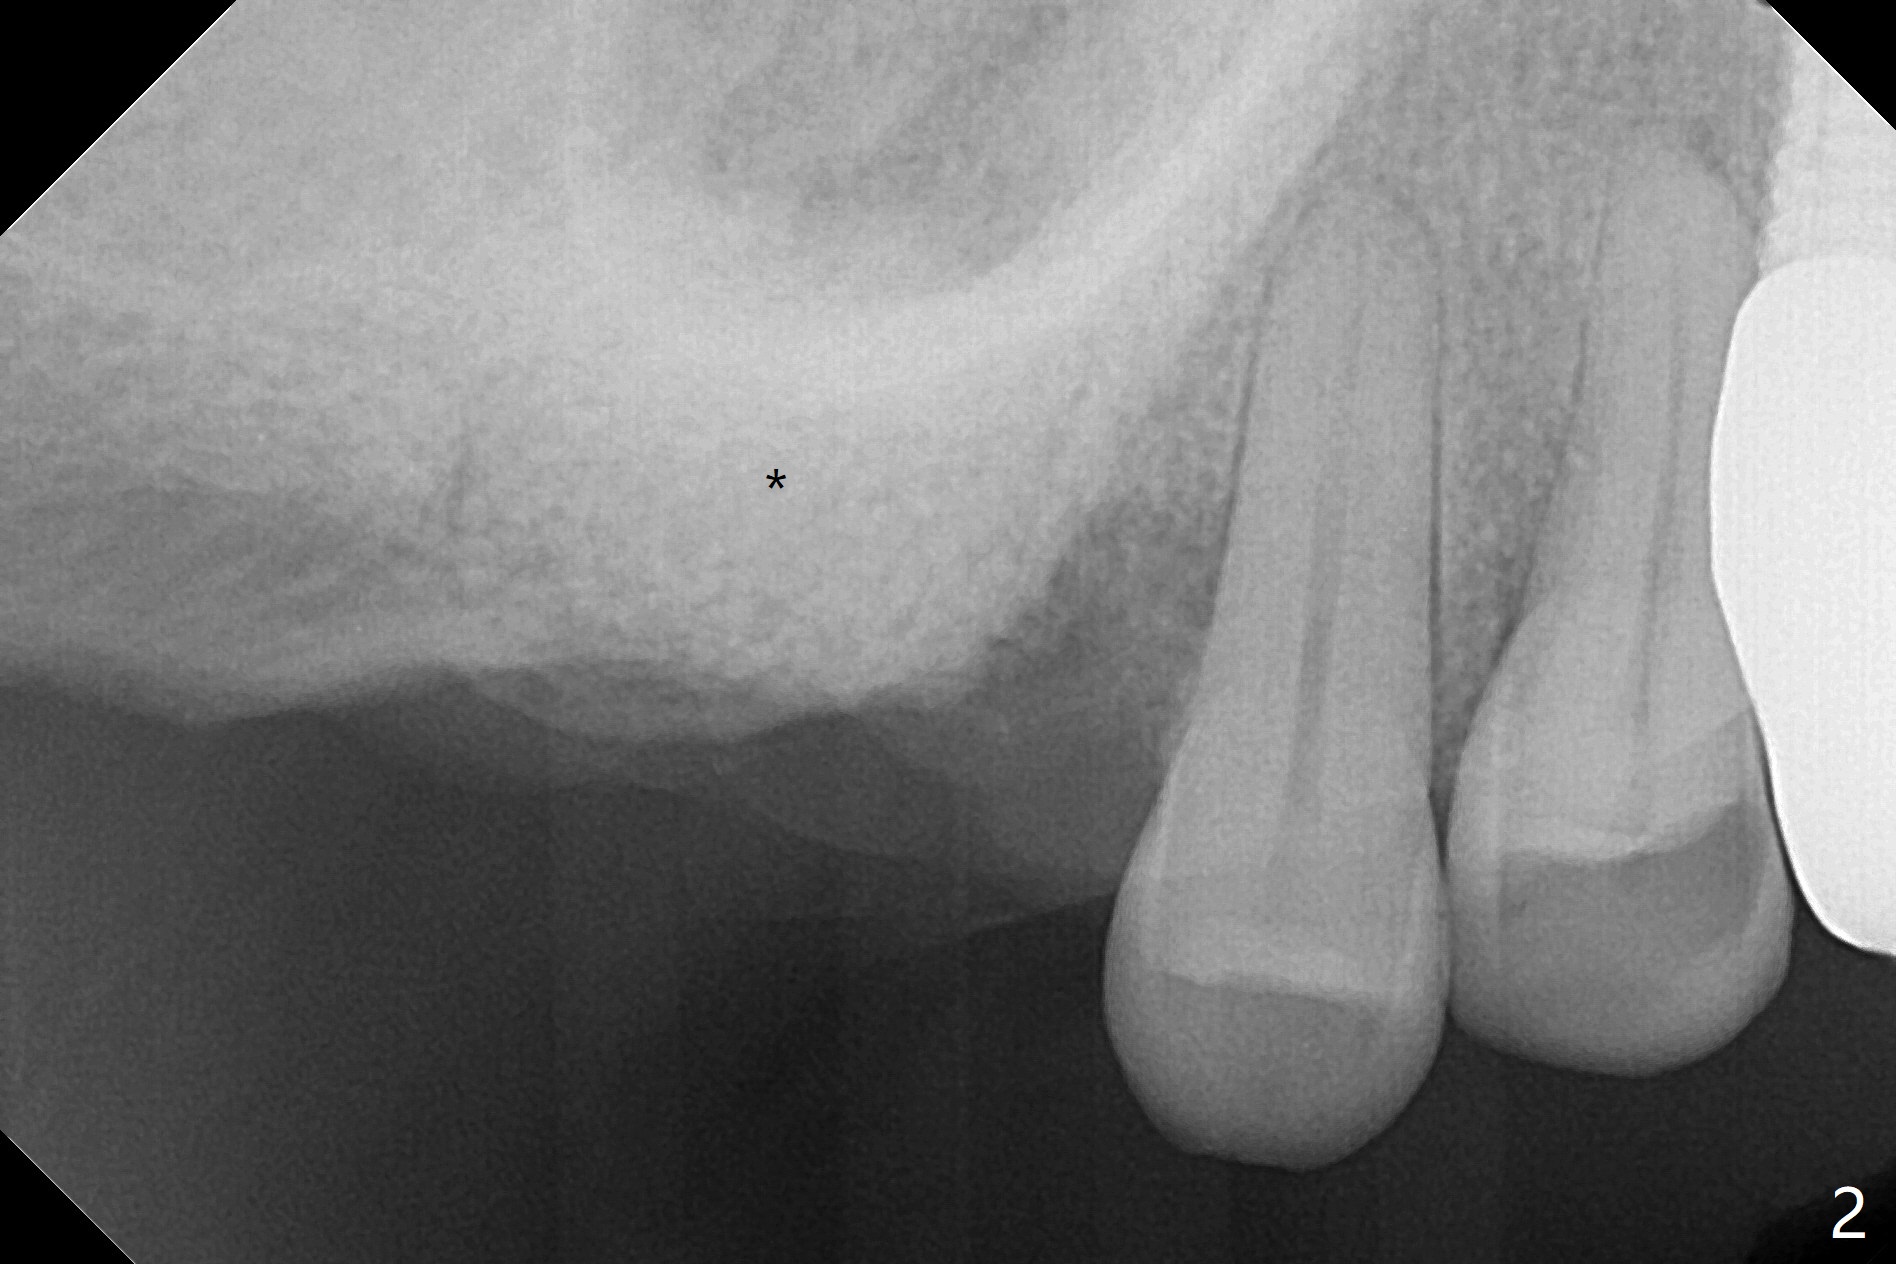

66岁男要求拔除2号牙(近中倾斜,3号牙缺失,图一),术中发现巨大骨质缺损,病人同意植骨(皮质骨,用血调袢,图二:*),覆盖Cytoplast,使用PTFE缝线,8字形缝合,两次。之后牙周敷料覆盖。术后十二天,敷料松动,但是不脱落,因为敷料与缝线粘连,牙龈好像已经固定不可吸收膜,不得不撤除缝线(图三)。Return to Protect Graft 下一个不使用敷料病例 位点保存 Xin Wei, DDS, PhD, MS 1st edition 06/12/2021, last revision 07/03/2021